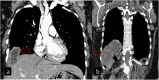

Hydatid cyst caused by the larval form of Echinococcus is a worldwide zoonosis. The lungs and liver are the most common sites involved. While the lung parenchyma is the most common site within the thorax, it may develop in any extrapulmonary region including the pleural cavity, fissures, mediastinum, heart, vascular structures, chest wall, and diaphragm. Imaging plays a pivotal role not only in the diagnosis of hydatid cyst, but also in the visualization of the extent of involvement and complications. The aim of this pictorial review was to comprehensively describe the imaging findings of thoracic hydatid cyst including pulmonary and very unusual extrapulmonary involvements. An outline is also given for the findings of complications and differential diagnosis of thoracic hydatid cyst.